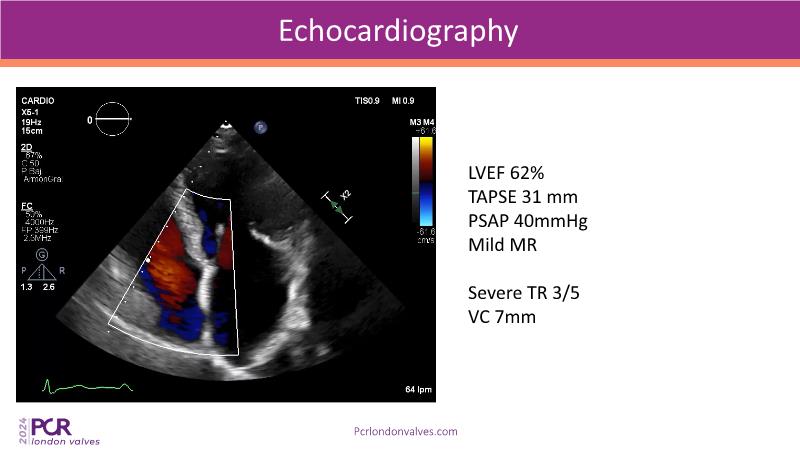

This session examines two compelling cases: a 78-year-old woman with paroxysmal atrial fibrillation, chest trauma, an osteoporotic sternum fracture, and NYHA II exertional dyspnoea, and an 82-year-old man with chronic three-vessel coronary artery disease, bradycardic AF, peripheral arterial disease, spinal stenosis, and chronic kidney disease. Through their study, discover the intricate anatomy of atrioventricular valves, the therapeutic challenges they pose, and the growing significance of transcatheter edge-to-edge repair (TEER) therapies. The discussion also highlights the value of multidisciplinary strategies in managing complex valve diseases effectively.